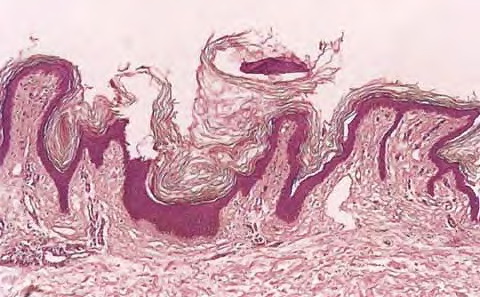

Read MoreAccessory Nipple =’الحلمة الاضافية OLYMPUS DIGITAL CAMERA OLYMPUS DIGITAL CAMERA OLYMPUS DIGITAL CAMERA Accessory Nipple The histologic features of a supernumerary nipple are identical to that of the regular nipple, including hyperpigmentation, slight hyperkeratosis with epidermal thickening, pilosebaceous structure of Montgomery areolar tubercles, smooth muscle bundles typical of the areola, and possible mammary glands […]